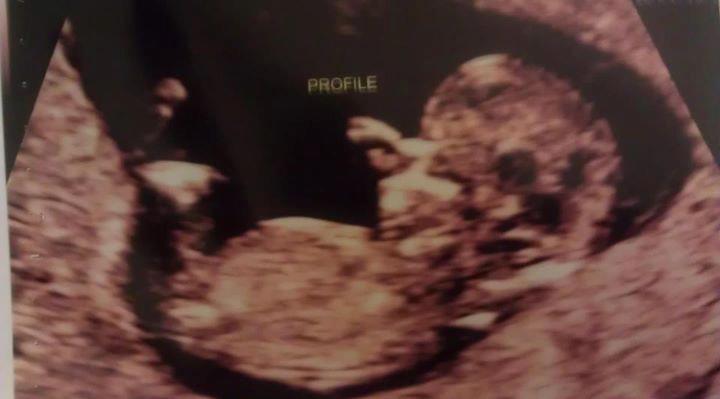

Hi all, im new here. Attaching two us photos from 12-13weeks. Can any one give me their guesses? Attachment 1737Attachment 1738

Ill love baby no matter what but I hope lo is a girl. This is our last lo we have two awesome sons already, I would lo to finally have my precious Princess. Thank you for the guesses so far!

I think girl based on the overall baby shape and head, theres no sign of a protruding nub so yeah girl good luck hun

Thinking girl based on the skull theory.

Maybe girl? (skull)

Maybe boy.